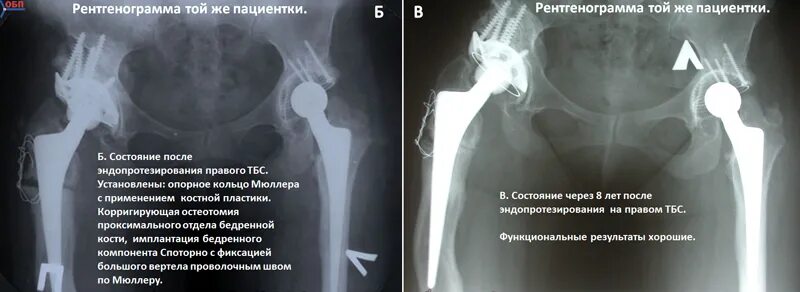

Срок службы тазобедренного эндопротеза